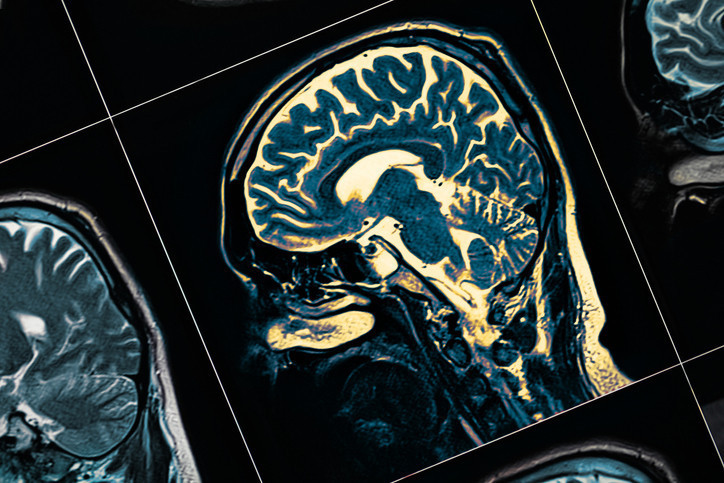

Demans, günlük yaşamı etkileyecek kadar şiddetli hafıza, dil, sorunları çözme ve diğer düşünme becerilerinin kaybını ifade eden genel bir terim. Zamanla sinir hücrelerini tahrip eden ve beyne zarar veren bir dizi hastalığın neden olabileceği bir sendrom. Genellikle bilişsel işlevlerde, yani düşünceyi işleme yeteneğinde biyolojik yaşlanmanın olağan sonuçlarından beklenenin ötesinde bir bozulmaya yol açıyor. Bilinç etkilenmese de bilişsel işlevlerdeki bozulmaya genellikle ruh hali, duygusal kontrol, davranış veya motivasyon değişiklikleri eşlik ediyor ve bazen de öncesinde görülüyor.

Demans denildiğinde ilk akla gelen Alzheimer olsa da aslında pek çok demans türü mevcut. Beyni etkileyen çeşitli hastalıklardan ve yaralanmalardan kaynaklanabilen demansın ek sık görülen tiplerini şöyle özetleyebiliriz:Alzheimer: Demansın yüzde 60-70 gibi yüksek bir oranı Alzheimer kaynaklı oluyor. Vasküler demans: Beyinde mikroskobik kanama ve kan damarı tıkanıklığı sonucu gelişiyor ve demansın en yaygın 2’inci sebebini oluşturuyor. Lewy cisimcikli demans: Sinir hücreleri içinde anormal protein birikmesi nedeniyle ortaya çıkıyor. Frontotemporal demans: Beyin ön lobunun dejenerasyonu sebebiyle görülüyor.